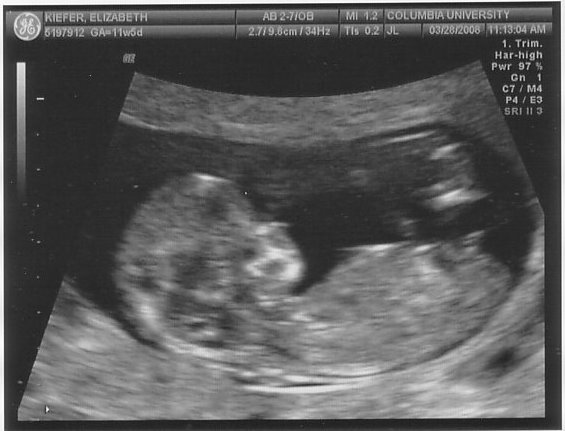

On Friday we headed uptown for our second ultrasound. Nobody told me that baby m0ves around in there at 12 weeks (thanks for the help, parenting books, keep up the good work!), so I just about freaked out when he arched his back and rubbed his face (or she/her, of course, we don’t find that out for another 6 weeks). Fortunately our tech was used to people gasping loudly. Sooooo cool.

In case you were wondering if I was going to be a stereotype of a dad, I’m including all 5 blurry blob pictures here. And if I had an hour long movie of same, I’d post that, too.